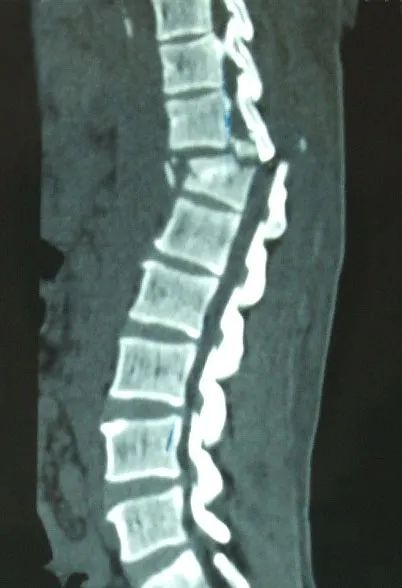

駝背、變矮、腰腿痛

您是否經(jīng)歷過骨折的痛楚?

手術(shù)、住院、難以動彈